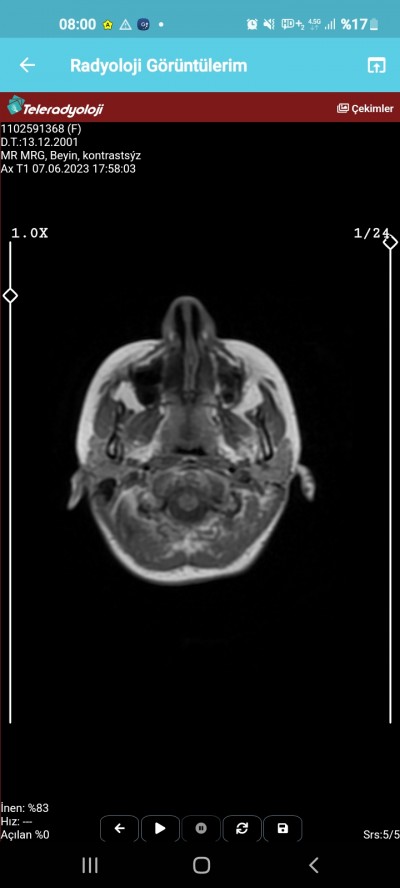

Kızlar sonuçları Çarşamba günü çıkacak başımda inanılmaz bir ağrı var dayanamıyorum artık dün gece çok şiddetlendi dayanamadım.

Lütfen anlayab varsa bakabilir mi bişey var mı

Hayır birşey gözükmüyor cnm eşimin beyninde tümör var böyle görüntü de baya belli sende elhamdülillah birşey yok geçmiş olsun

Mr 100 kusur tane görüntü ile oluşan bir görüntü 3 tane görüntü ile anlamak imkansız ve rapor artı doktorun görmesi lazım rapor cikmis olsa gene biseyler diyebilirdim